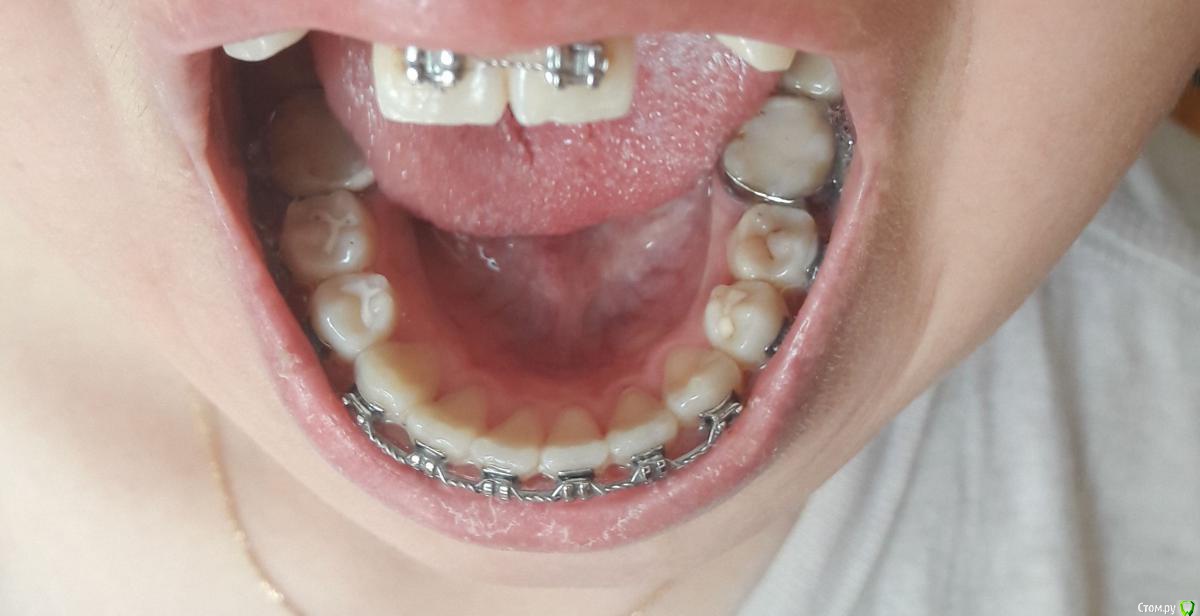

Амина Опубликовано 4 июня, 2016 Автор Поделиться Опубликовано 4 июня, 2016 вот снимок 2016 года Ссылка на комментарий

Амина Опубликовано 4 июня, 2016 Автор Поделиться Опубликовано 4 июня, 2016 Это снимок 2015 года Ссылка на комментарий